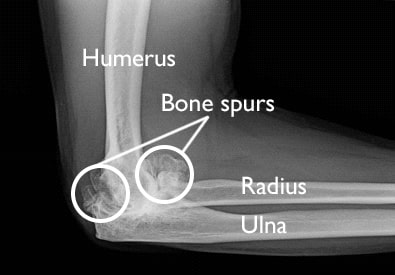

The ulnar collateral ligament (UCL) is a connective tissue that connects the humerus (upper arm bone) to the ulna (lower arm bone). When the UCL is fully or partially torn, the elbow does not have the ability to withstand significant amounts of valgus stress, causing pain and instability in the medial (inside) elbow.

- Bone spur removal – Many pitchers will have bone chips and/or spurs floating around in the elbow region. While these boney bodies don’t always require removal on their own, most surgeons will opt to clean them out while they are already working in the elbow.